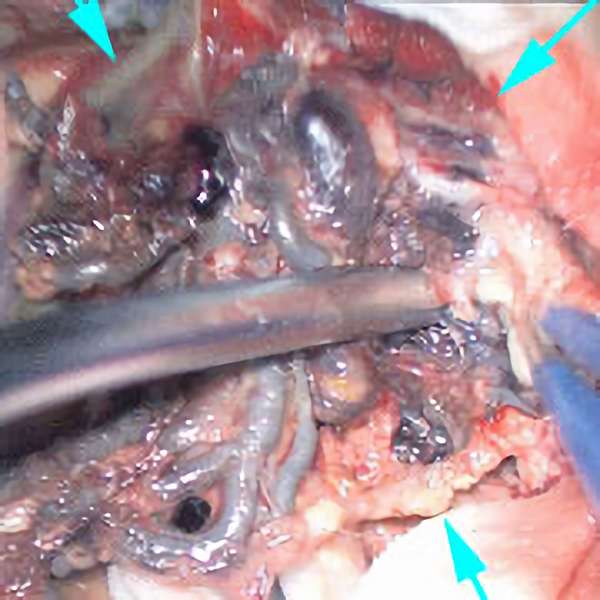

No.452 手術中